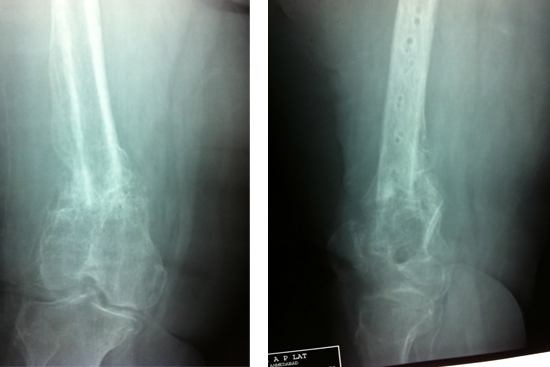

Non Union Femur

Case 2 (Rampyari)